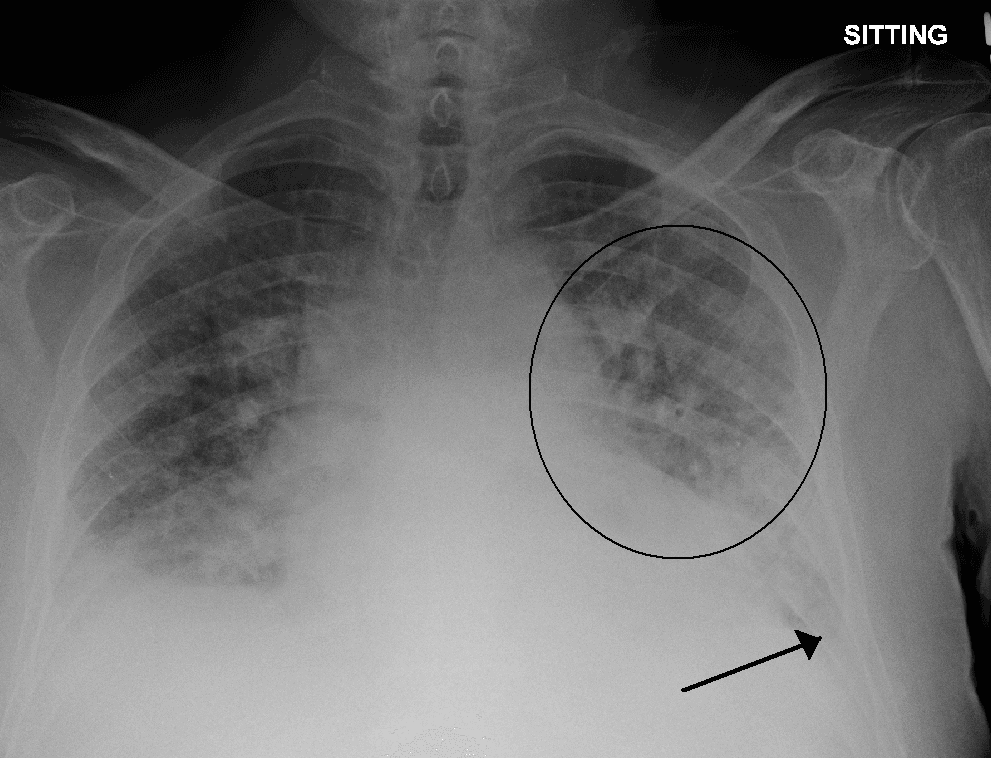

Pulmonary edema, also known as pulmonary congestion, is excessive liquid accumulation in the tissue and air spaces (usually alveoli) of the lungs. It leads to impaired gas exchange and may cause hypoxemia and respiratory failure. It is due to either failure of the left ventricle of the heart to remove oxygenated blood adequately from the pulmonary circulation (cardiogenic pulmonary edema), or an injury to the lung tissue directly or blood vessels of the lung (non-cardiogenic pulmonary edema). Treatment is focused on three aspects: firstly improving respiratory function, secondly, treating the underlying cause, and thirdly preventing further damage and assuring full recovery to the lung. Pulmonary edema, especially when sudden (acute), can lead to respiratory failure or cardiac arrest due to hypoxia. It is a cardinal feature of congestive heart failure. The term edema is from the Greek οἴδημα (oidēma, "swelling"), from οἰδέω (oidéō, "(I) swell"). Classically it is cardiogenic (left ventricular) but fluid may also accumulate due to damage to the lung. This damage may be from direct external injuries or injuries mediated by high pressures within the pulmonary circulation. When directly or indirectly caused by increased left ventricular pressure, pulmonary edema may form when mean pulmonary pressure rises from the normal average of 15 mmHg to above 25 mmHg, where pulmonary fluid may form. Broadly, the causes of pulmonary edema can be divided into cardiogenic and non-cardiogenic. By convention, cardiogenic specifically refers to left ventricular causes. Congestive heart failure which is due to the heart's inability to pump the blood out of the pulmonary circulation at a sufficient rate resulting in elevation in pulmonary wedge pressure and edema – this usually is due to left ventricular failure, but may also be from arrhythmias, or fluid overload, (e.g. from kidney failure or intravenous therapy). Hypertensive crisis can cause pulmonary edema as the elevation in blood pressure and increased afterload on the left ventricle hinders forward flow in blood vessels and causes the elevation in wedge pressure and subsequent pulmonary edema.